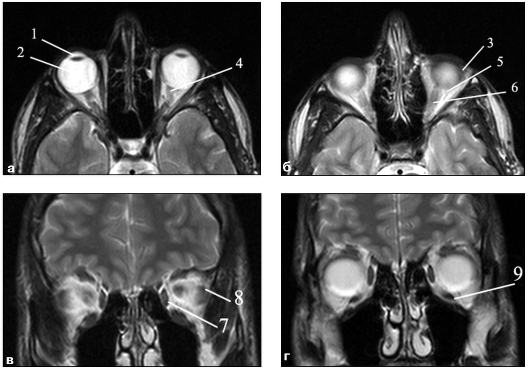

Костные стенки глазниц дают выраженный

гипоинтенсивный сигнал на Т1-ВИ и на Т2-ВИ. Глазное яблоко состоит из оболочек

и оптической системы. Оболочки глазного яблока (склера, сосудистая оболочка и

сетчатка) визуализируются в виде четкой темной полоски на Т1-ВИ на Т2-ВИ,

окаймляющей глазное яблоко как единое целое. Из элементов оптической системы на

МР-томограммах видны передняя камера, хрусталик и стекловидное тело (см. рис.

5).

Рис. 5. МР-томограмма глаза в норме: 1 -

хрусталик; 2 - стекловидное тело глазного яблока; 3 - слезная железа; 4 -

зрительный нерв; 5 - ретробульбарное пространство; 6 - верхняя прямая мышца; 7

- внутренняя прямая мышца; 8 - наружная прямая мышца;9 - нижняя прямая мышца

Передняя камера содержит водянистую влагу,

вследствие чего дает выраженный гиперинтенсивный сигнал на Т2-ВИ. Хрусталику

свойствен выраженный гипоинтенсивный сигнал и на Т1-ВИ, и на Т2-ВИ, так как он

представляет собой полутвердое бессосудистое тело. Стекловидное тело дает

повышенный МР-сигнал на Т2-ВИ и пониженный - на Т1-ВИ. МР-сигнал рыхлой

ретробульбарной клетчатки имеет высокую интенсивность на Т2-ВИ и низкую - на

Т1-ВИ.

Экстраокулярные мышцы на МР-томограммах по

интенсивности МР-сигнала значительно отличаются от ретробульбарной клетчатки,

вследствие чего четко визуализируются на всем протяжении. Четыре прямые мышцы с

однородным изоинтенсивным сигналом начинаются от сухожильного кольца и

направляются по бокам от глазного яблока к склере.